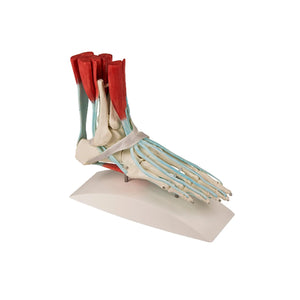

Squelette du pied humain

Squelette de pied grandeur nature montrant les tendons et les muscles qui leur sont attachés. Tous les os du pied sont représentés individuellement. Les muscles avec tendons suivants sont présents : long fléchisseur des orteils, tibial postérieur, long fléchisseur de l'hallux, long péronier, court péronier, long extenseur de l'hallux, long extenseur des orteils et tibial antérieur, Ret. musculorum peroneorum superiorius, Ret. Extensorum inferius, M. soleus, M. flexor digitorum brevis. Avec trépied amovible et carte-clé en latin, allemand et anglais.

Squelette du pied humain

Squelette de pied grandeur nature montrant les tendons et les muscles qui leur sont attachés. Tous les os du pied sont représentés individuellement. Les muscles avec tendons suivants sont présents : long fléchisseur des orteils, tibial postérieur, long fléchisseur de l'hallux, long péronier, court péronier, long extenseur de l'hallux, long extenseur des orteils et tibial antérieur, Ret. musculorum peroneorum superiorius, Ret. Extensorum inferius, M. soleus, M. flexor digitorum brevis. Avec trépied amovible et carte-clé en latin, allemand et anglais.

Squelette du pied avec muscles

Avec représentation des ligaments et du muscle.